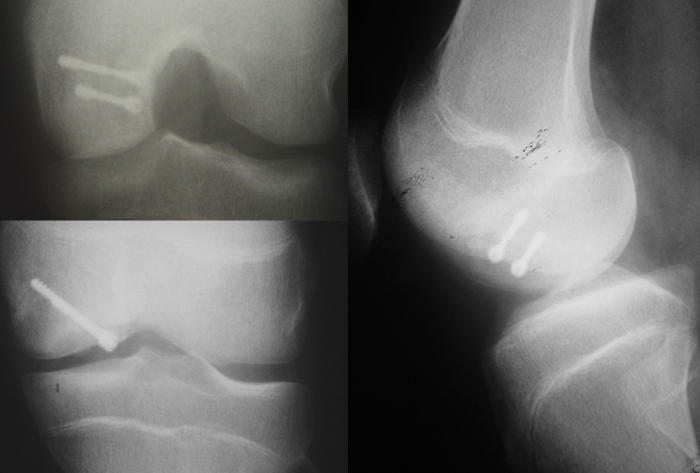

Osteokondritis dissekans tanısı için ortopedi doktorunuzun yapacağı ayrıntılı bir diz muayenesi sonrası röntgen grafileri hastaların çoğunda yeterlidir (Resim 1). Bilgisayarlı tomografi (BT) ve Manyetik Rezonans Görüntüleme (MRG) gibi ileri görüntüleme yöntemleri hastalığın evresinin belirlenmesi, tedavi planının yapılması ve tedavi sonucunun değerlendirilmesi için gereklidir (Resim 2). Artroskopik değerlendirme, evreleme ve tedavi planı için en önemli araçtır. Bir kamera kullanılarak eklem içi incelenir, parçanın boyutları, yerleşimi, altındaki yatağa olan bağlantısı ve vida tespitine uygun olup olmadığı nihai olarak artroskopi sırasında değerlendirilir ve tedavi aşamasına geçilir.

Kıkırdak devamlılığı bozulmuş ve oynar hale gelmiş, ancak hala yatağına yumuşak doku bağlantıları ile tutunan osteokondritis dissekans parçaları vida ile tespit edilebilir (Video 1). Bunun için önce parça kapak gibi kaldırılır, altındaki iyileşmeyi engelleyen yumuşak dokular kazınarak çıkartılır ve canlı kemik yüzeyleri ortaya konur. Gerekirse komşu kemiklerden alınan canlı kemik parçaları (kemik grefti) yatağın içine yerleştirilir. Bu eklenen kemikler hem eklem yüzeyinin uygun şekilde oluşmasına destek olur hem de iyileşmeyi artırıcı etkiye sahiptir. Sonrasında kapak şeklindeki parça yerine yerleştirilip, en az iki vida ile tespit edilir (Resim 4). Bu tespit için metal veya zaman içinde çözünen biyovidalar kullanılabilir. Metal vidaların tespit sağlamlığı daha fazladır, ancak birkaç ay sonra ikinci bir ameliyat ile çıkartılmaları gerekir.